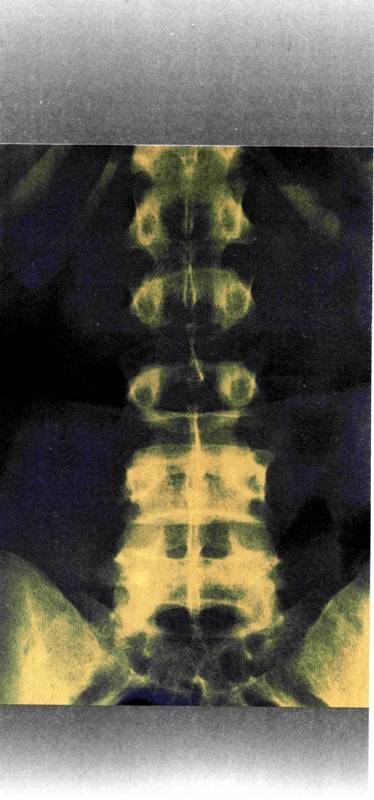

Ακτινογραφία οσφυϊκής μοίρας σπονδυλικής στήλης (χρωματικά επεξεργασμένη)